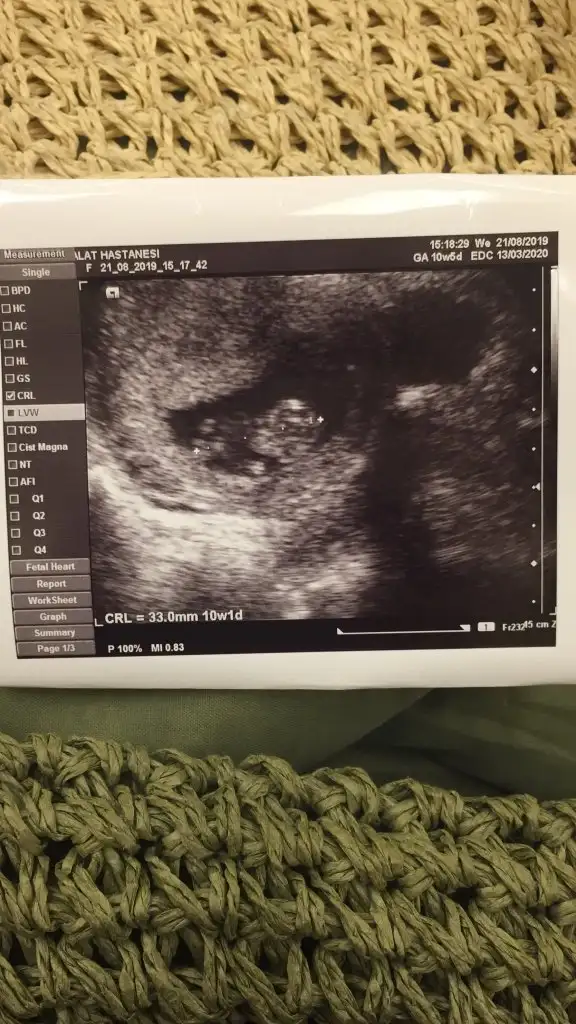

merhaba herkese, lütfen birde benim için tahminde bulunun 11.haftadayım

Eklentiler

• IMG_20190823_182521.webp

27,8 KB · Görüntüleme: 63